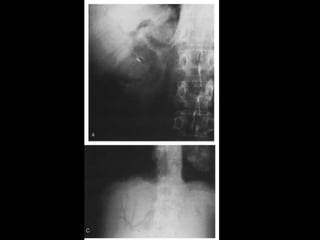

• Rx:

– 10 – 15% das colelitiases, estão calcificadas e

identificáveis no RX

– Pode ser visto também a vesícula em “porcelana.”

– Gás pode ser visto dentro das pedra: Sinal de

Mercedes-Benz

– Colecistografia oral: Ingesta de composto iodado.

Atualmente susbstituído pelo US

Técnicas de Imagem •Rx: – 10 – 15% das colelitiases, estão calcificadas e identificáveis no RX – Pode ser visto também a vesícula em “porcelana.” – Gás pode ser visto dentro das pedra: Sinal de Mercedes-Benz – Colecistografia oral: Ingesta de composto iodado. Atualmente susbstituído pelo US